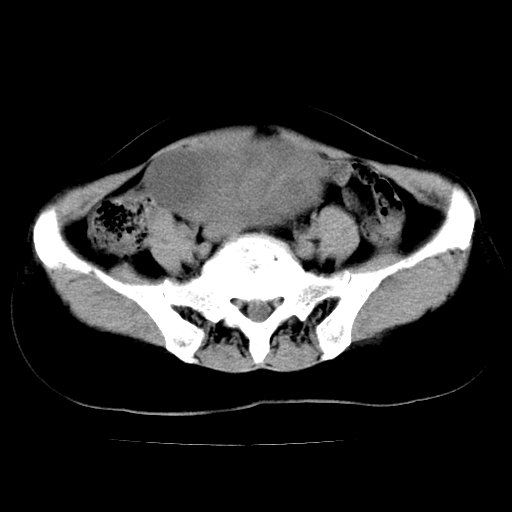

标题: CT24785:女,62岁,发现下腹部肿物半年。 [打印本页]

女,62岁,发现下腹部肿物半年,下腹部不适。

老年女性患者,盆腔囊实性占位,ct增强不均匀强化,未见壁结节,未见腹水及盆腔积液,考虑附件囊腺瘤可能性大!

考虑肠系膜间质肉瘤或脐尿管癌可能性大。

考虑回肠间质瘤,不排除卵巢癌可能。

考虑子宫平滑肌肉瘤可能性大。

考虑附件粘液性囊腺瘤可能性大。

实性成分太多,要是囊腺瘤也要考虑恶性。